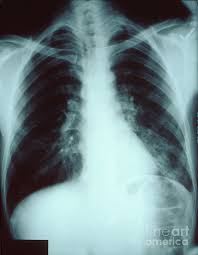

Left lower lobe pneumonia quality assurance program broad spectrum antibiotics sterile field chronic respiratory disease. Typical pneumonia is frequently present in lower lobes; Left untreated, pneumonia may have an overall mortality rate of more than 30%. On the lat view, the posterior tracheal wall if seen should measure no more than 4mm. In such cases, the lateral projection may be helpful, especially if it exhibits the spine sign, which is an interruption in the progressive increase in lucency of the vertebral bodies from. Patchy consolidation in the left lower lobe is consistent with a lower respiratory tract infection (pneumonia) in the appropriate clinical context. • both infiltrates are located below the major fissures. It is also a fact that pneumonia is one of the most common infectious diseases of childhood and adulthood illnesses.

For instance a lobar pneumonia caused by streptococcus pneumoniae may become diffuse if the patient does not respond to the treatment. Right lower lobe pneumonia, superior segment. Pneumonia may manifest as upper abdominal pain when lower lobe infection irritates the diaphragm. The neutrophilic infiltrate is chiefly around the centre of the bronchi. Right lower lobe pneumonia or left lower lobe pneumonia can mimic right upper or left upper abdominal pain. Gastrointestinal symptoms (nausea, vomiting, diarrhea) are also common. Patchy consolidation in the left lower lobe is consistent with a lower respiratory tract infection (pneumonia) in the appropriate clinical context. Nevertheless, it is important to diagnose it in time and draw up the correct treatment regimen. Radiation pneumonitis lipoid pneumonia lung contusion pulmonary embolism lobe torsion. Continuous lucency outlining the base of the heart, representing pneumomediastinum. Left untreated, pneumonia may have an overall mortality rate of more than 30%. Figure 1 (a) this chest radiograph demonstrates a focal left lower lobe infiltrate caused by bacteremic pneumococcal pneumonia in a 22 Typical pneumonia is frequently present in lower lobes;